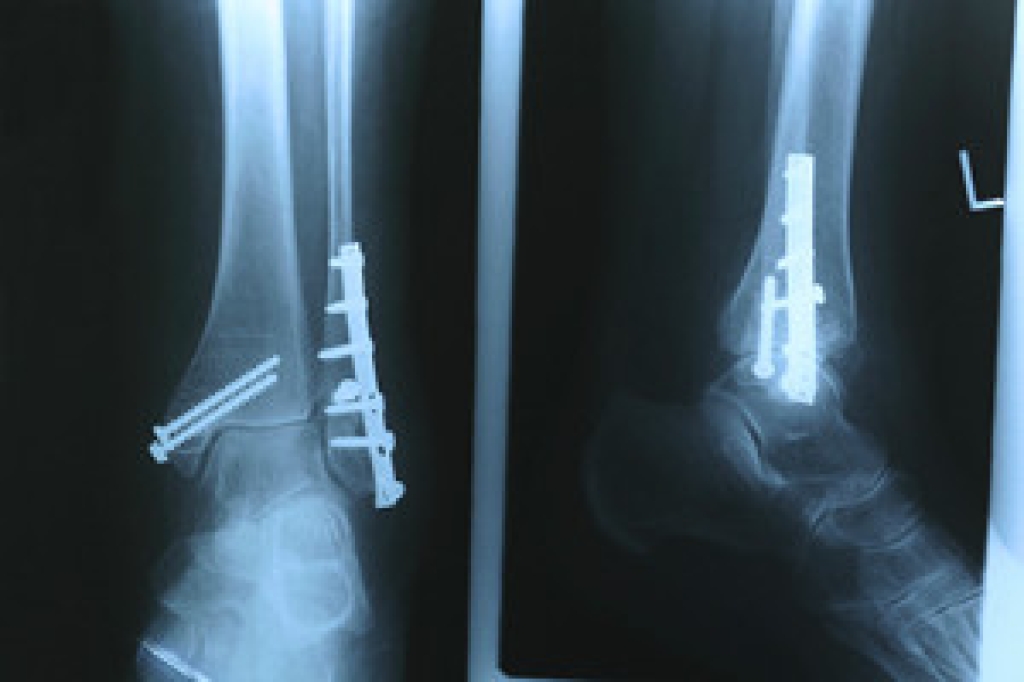

A broken ankle is experienced when a person fractures their tibia or fibula in the lower leg and ankle area. Both of these bones are attached at the bottom of the leg and combine to form what we know to be our ankle.

When a physician is referring to a break of the ankle, he or she is usually referring to a break in the area where the tibia and fibula are joined to create our ankle joint. Ankles are more prone to fractures because the ankle is an area that suffers a lot of pressure and stress. There are some obvious signs when a person experiences a fractured ankle, and the following symptoms may be present.